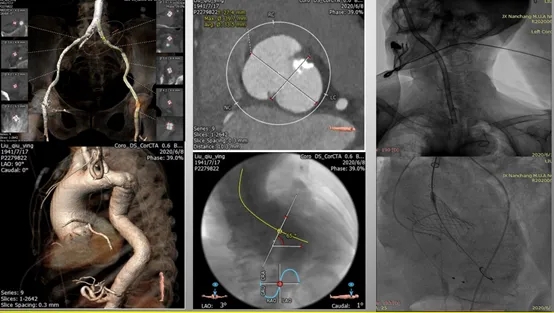

对于存在入路困难的患者行TAVR,应基于术前详细的影像学评估结果选择最适宜的入路方式。目前,我国TAVR手术中超过80%采用经股动脉入路。

然而,当患者存在股动脉管腔严重狭窄、血管显著迂曲或重度钙化等不适合TF入路的情况时,应考虑采用其他替代入路策略,包括颈动脉入路、锁骨下/腋动脉入路、经心尖入路、经升主动脉入路以及经腔静脉入路等。

经心尖部入路TAVR